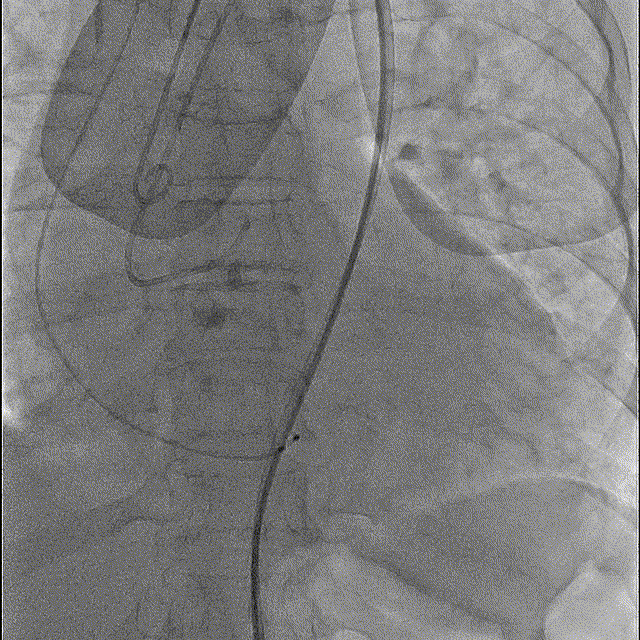

左冠造影

右冠造影